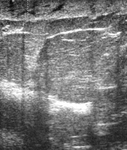

Imagen en ultrasonografía de engrosamiento cutáneo en paciente con cáncer de mama inflamatorio

Cortesía de la Dra. Nancy Pile, University of Louisville; utilizada con autorización

Ver esta imagen en el contexto de la/s siguiente/s sección/es: